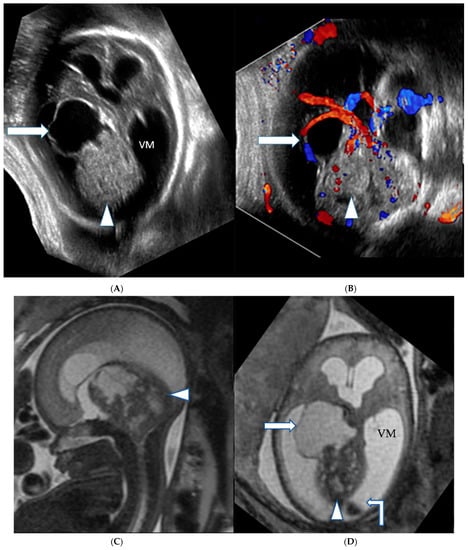

2. Case Series